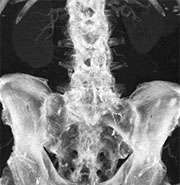

dual energy original

Original contrast-enhanced data set. The vascular anatomy is obscured by bony structures.